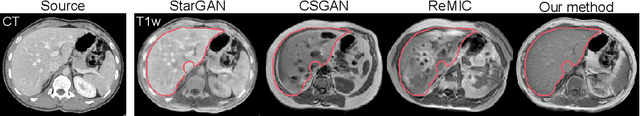

Abstract:Paired multi-modality medical images, can provide complementary information to help physicians make more reasonable decisions than single modality medical images. But they are difficult to generate due to multiple factors in practice (e.g., time, cost, radiation dose). To address these problems, multi-modality medical image translation has aroused increasing research interest recently. However, the existing works mainly focus on translation effect of a whole image instead of a critical target area or Region of Interest (ROI), e.g., organ and so on. This leads to poor-quality translation of the localized target area which becomes blurry, deformed or even with extra unreasonable textures. In this paper, we propose a novel target-aware generative adversarial network called TarGAN, which is a generic multi-modality medical image translation model capable of (1) learning multi-modality medical image translation without relying on paired data, (2) enhancing quality of target area generation with the help of target area labels. The generator of TarGAN jointly learns mapping at two levels simultaneously - whole image translation mapping and target area translation mapping. These two mappings are interrelated through a proposed crossing loss. The experiments on both quantitative measures and qualitative evaluations demonstrate that TarGAN outperforms the state-of-the-art methods in all cases. Subsequent segmentation task is conducted to demonstrate effectiveness of synthetic images generated by TarGAN in a real-world application. Our code is available at https://github.com/2165998/TarGAN.